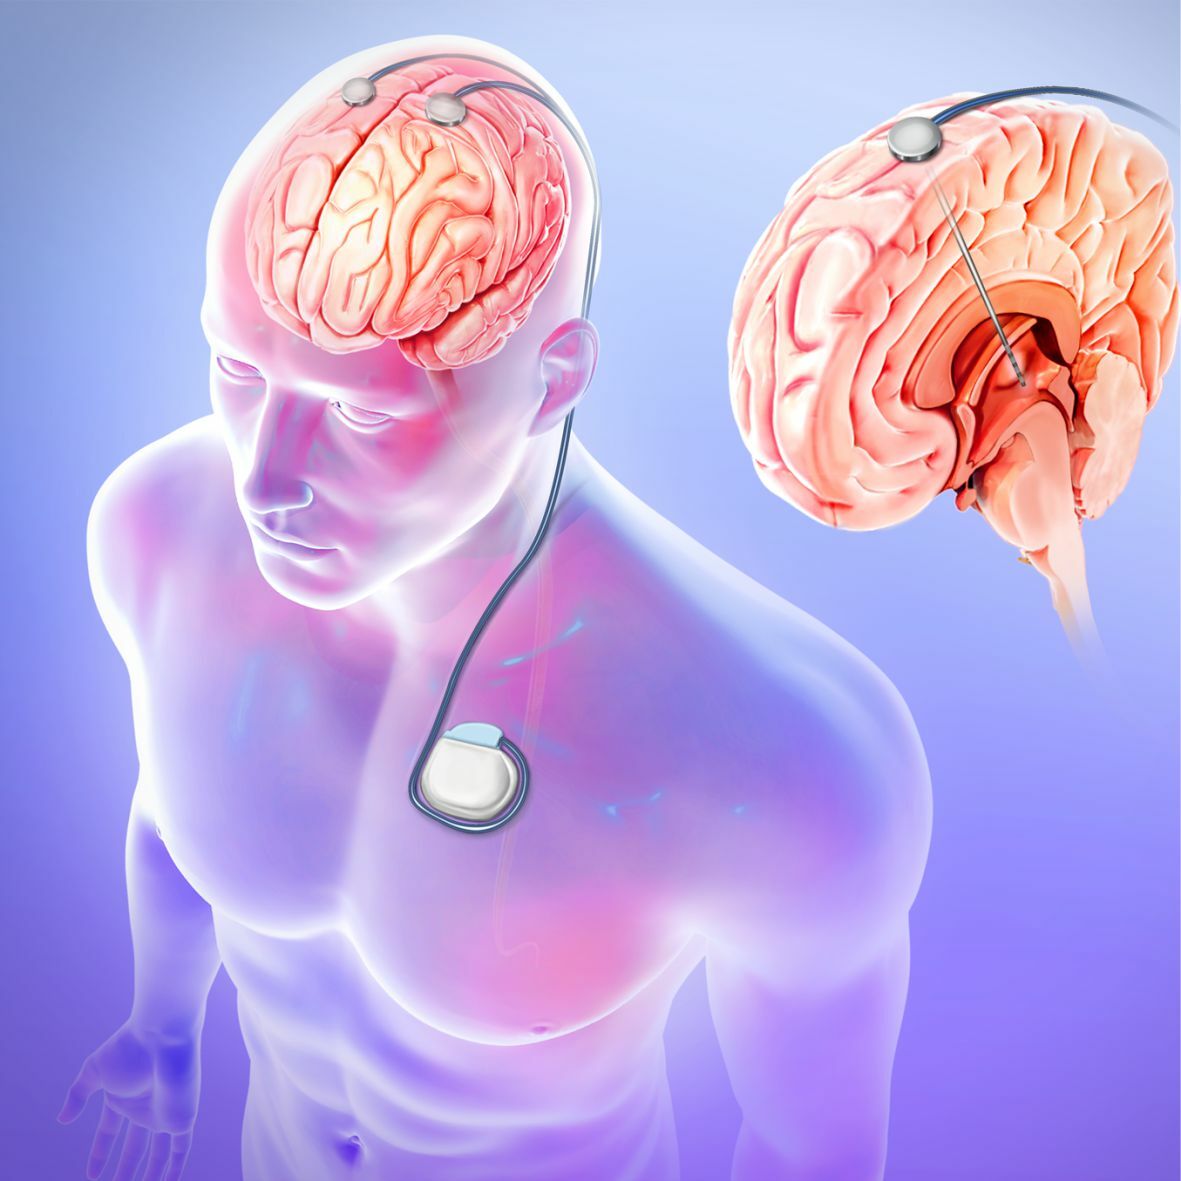

Анатомия мозга: Рентгеновские снимки для презентаций